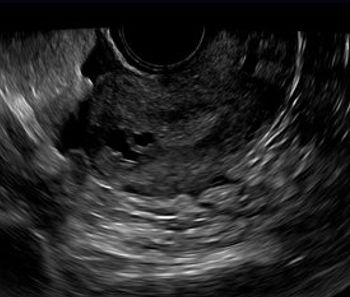

This is a confirmed case of scar ectopic pregnancy. Yesterday, I carried out this exam in an emergency room, without much time to perform an adequate sonogram, the patient did not feel good with “cramps” but no signs of bleeding.

Implantation in the scar of a previous Cesarean is thought to be the rarest of ectopic pregnancies. With the increasing numbers of Cesareans performed, scar implantation may become more frequent as well. We present an illustrative case.